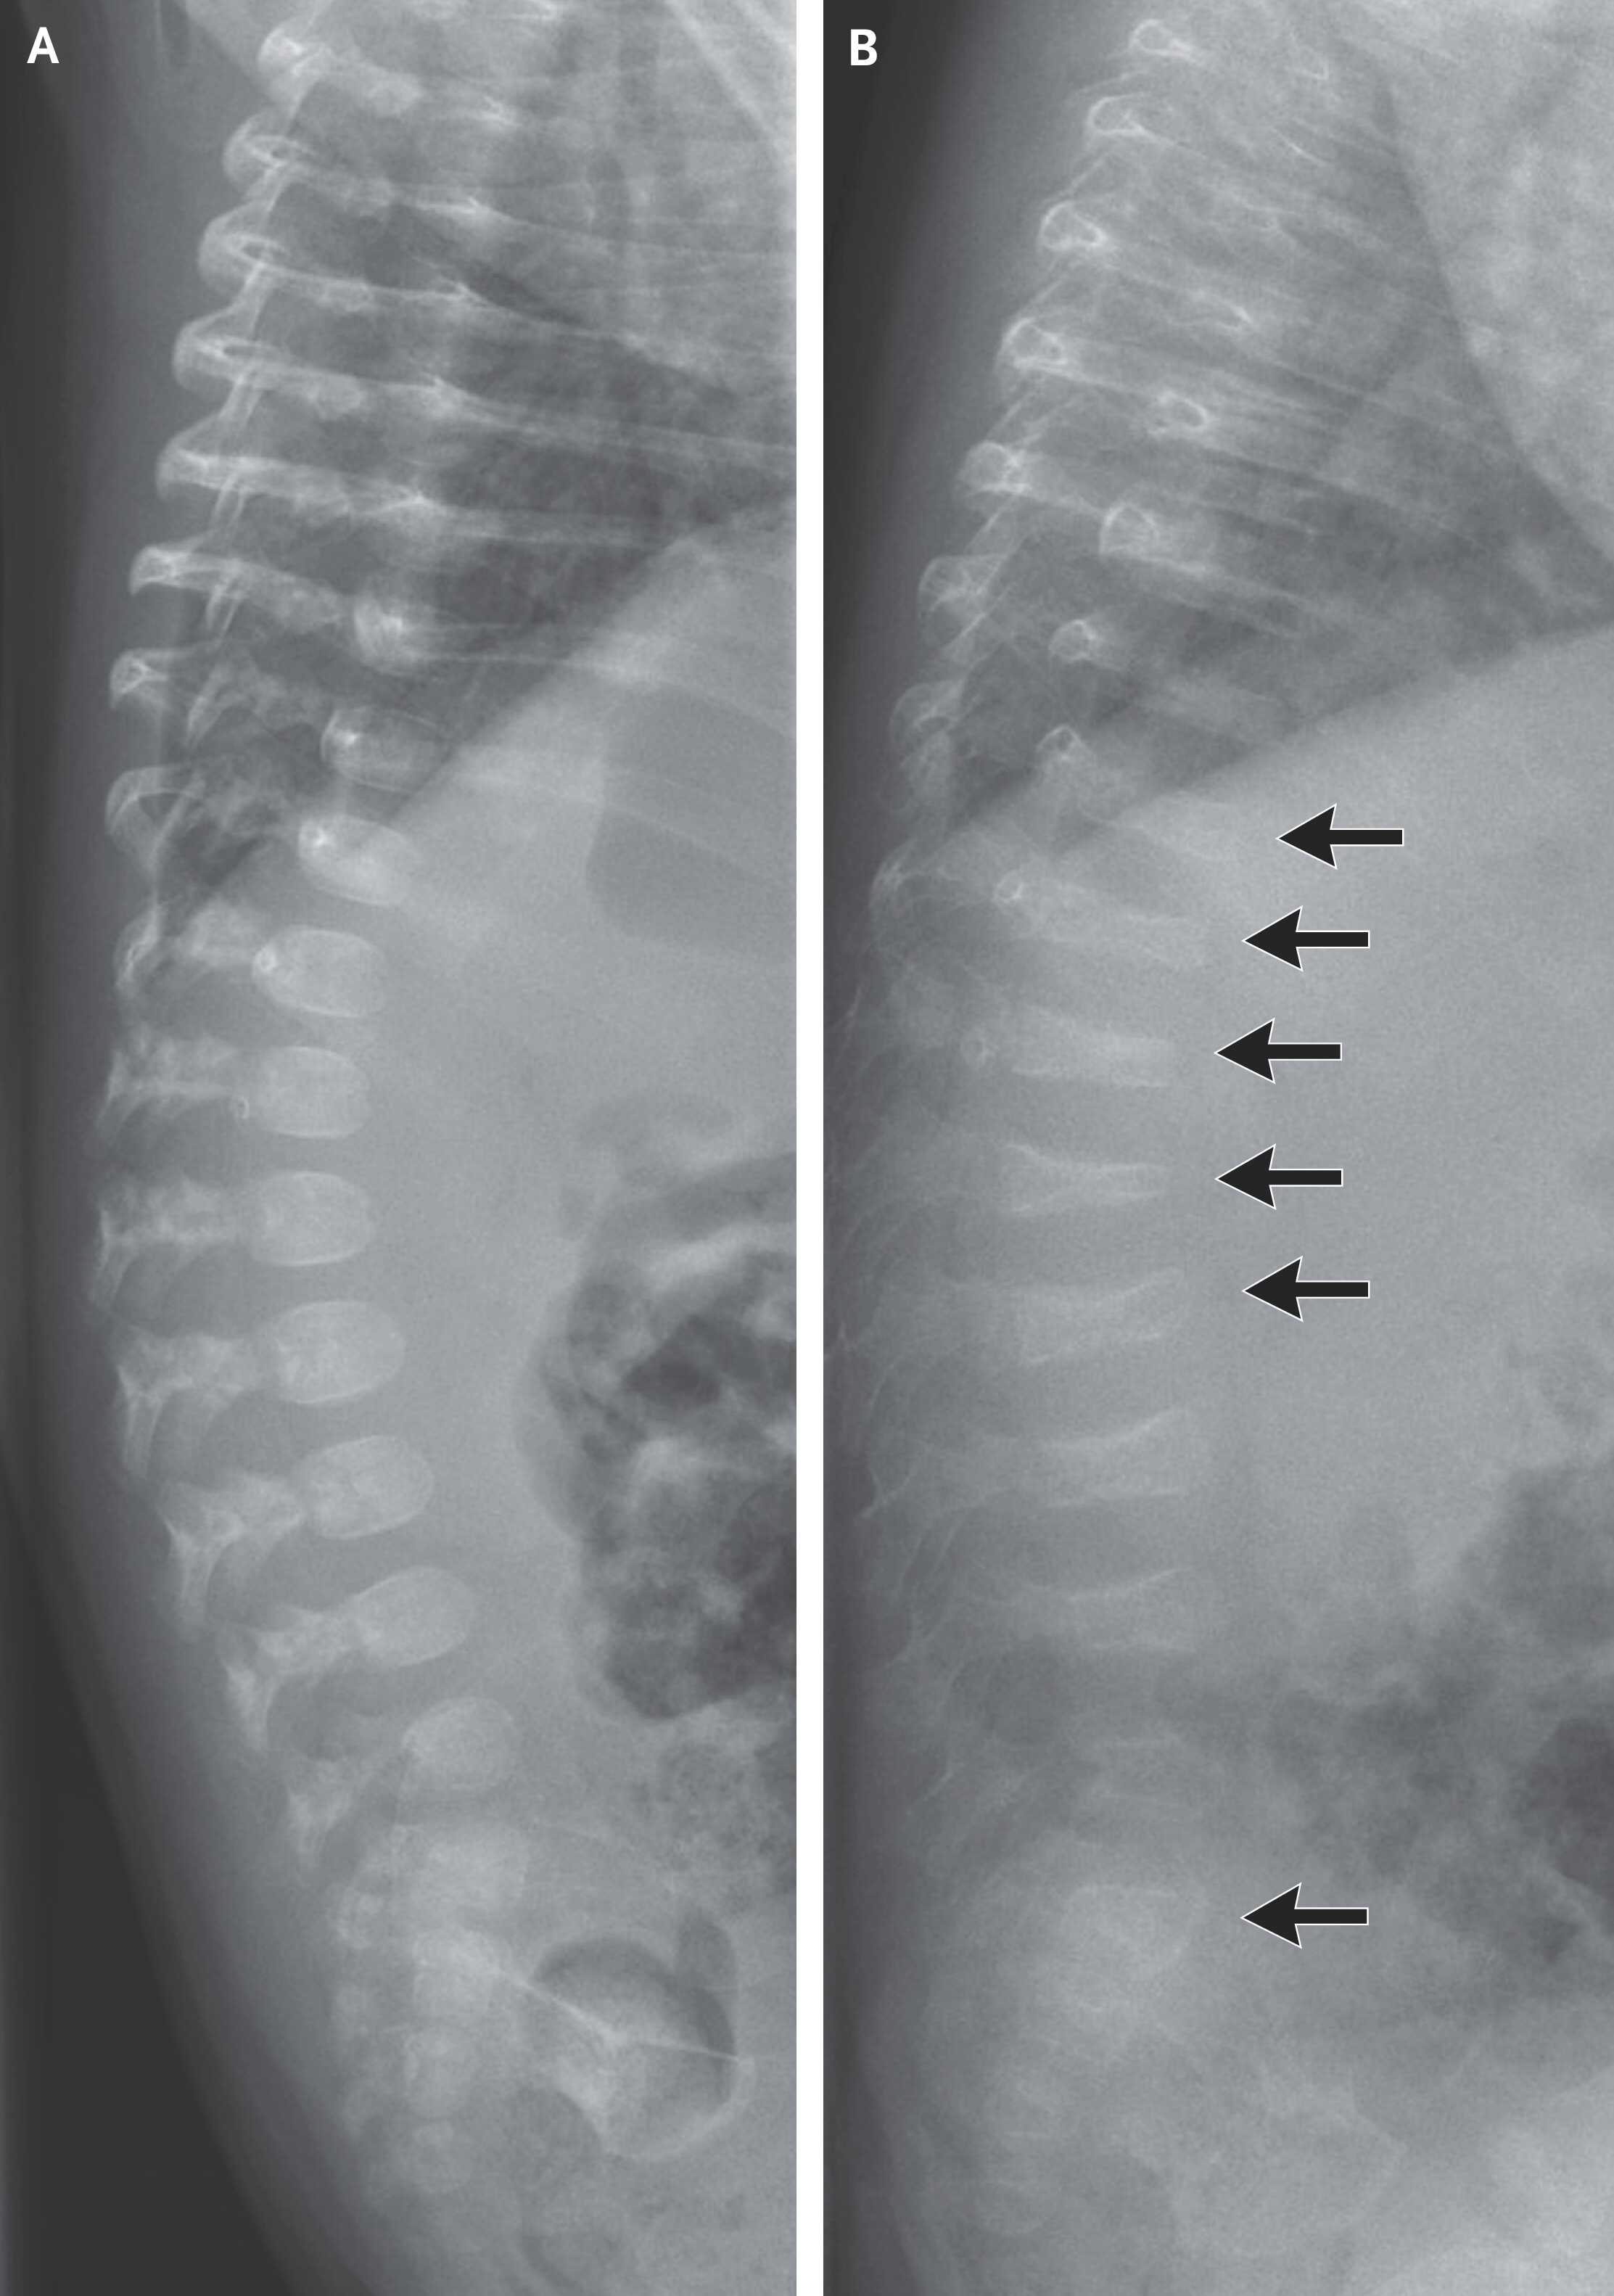

В последующие 2,5 месяца появились новые спонтанные переломы плечевых и бедренных костей. На повторной рентгенограмме позвоночника в 3,5 месяца были видны выраженное снижение костной массы и компрессионные переломы позвонков. Генетическое тестирование определило миссенс-мутацию гена COL1A1, кодирующего коллаген первого типа. На основании данных обследования младенцу поставили диагноз несовершенного остеогенеза третьего типа — врожденного прогрессирующего нарушения формирования костной ткани из-за недостаточного качества коллагена. В тяжелых случаях он может приводить к компрессии позвонков еще до появления гравитационной нагрузки, связанной с сидением и стоянием. В пятимесячном возрасте пациенту назначили ежеквартальные инфузии бифосфонатов (ингибиторов резорбции косной ткани). За восемь месяцев с момента первой инфузии у него появился только один новый перелом.